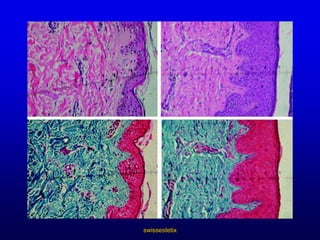

Lebensumstän-de und HabitsswissestetixVeränderungen der HautDie Altersveränderungen der Haut sind hauptsächlich Ausdruck der allgemeinen Degeneration des Bindegewebes.Atrophie der PapillarkörperAbnahme der Langerhans-ZellenAbnahme der FibroblastenAbnahme der Kapillaren

swissestetixUnvermeidlich – Alterungsprozess der HautZellaufbau der jungen HautZellaufbau der älteren HautOberhaut (Epidermis)Lederhaut(Dermis)

swissestetixÄnderungen der alternden HautEreignisseEpidermis……….   Dichte, Anz. Zellen, Melanozyten, Langerhans-ZellenDermis……………  Dichte, Anz. Zellen(z.B. Fibroblasten), BlutgefässeSonstige………...   Schweiß-, Talgdrüsen, HaarfollikelFolgen für die Funktion der HautWundheilung, Immunität, Bräunung, Elastizität, Dicke                  Infektion, Rauhigkeit, Trockenheit, Krebs, Fragilität, FALTEN